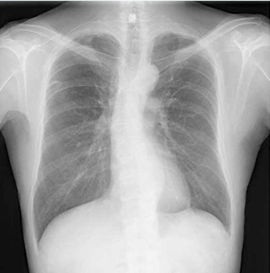

先端巨大症:糖尿病性ケトアシドーシスがきっかけで診断された症例ですが、耐糖能異常や血圧高値と顔貌から疾患を想起します。

34歳男性。糖尿病性ケトアシドーシス(DKA)で入院してきたところ、「顔が特徴的(広がった鼻・前頭部の隆起・突出した下顎・上切歯の不整咬合)」であることに代謝内…